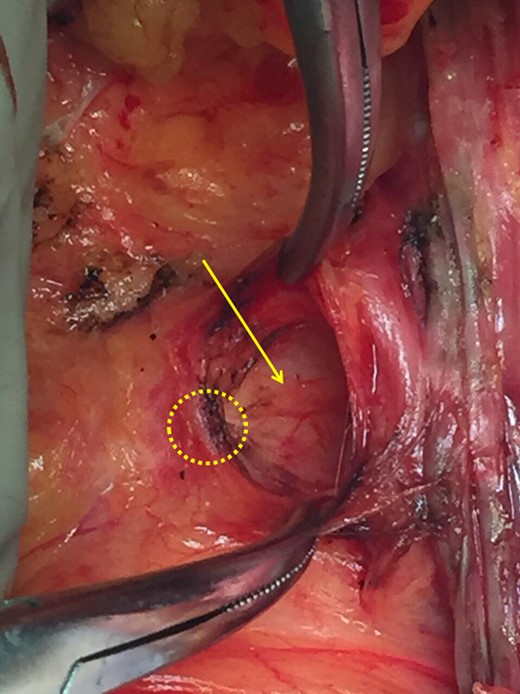

Following these, mammography was performed but it was not helpful due to the location of the mass. The breast ultrasound (U/S) and the U/S of the axilla detected a hypoechoic mass in the axillary fossa. MRI was also conducted, confirming a single lesion in the left axilla. There were no additional lesions seen in the same or contralateral breast on MRI (Fig. 1). Subsequent core needle biopsy (FNAB) established the diagnosis of breast infiltrating ductal carcinoma (Not otherwise specified), grade 2. Based on this a decision was made to proceed to quadrantectomy.During the surgery, the tumor was detected superficial to the clavipectoral fascia (Figs 2–4). A quadrantectomy was performed along with axillary lymph node block dissection since the sentinel node was positive for metastasis. The rest of the operation continued in the usual fashion. A drain was placed at the end of the procedure. The post-operative recovery was uneventful. The patient was discharged five days after the surgery, when the drain was finally removed.

The diagnostic question could only be answered during surgery. The mass was located superficial to the clavipectoral fascia and therefore a diagnosis of adenocarcinoma of the tail of Spence was established. Had we assumed that the patient had occult breast cancer with lymph node metastasis, she would have received neo-adjuvant chemotherapy that would have altered her stage and prognosis.

With this present case we attempt to underline the importance of the clavipectoral fascia and its diagnostic use as the sole anatomical boundary. According to our observations, any histologically confirmed axillary breast malignancy that is found superficial to the clavipectoral fascia confirms an axillary tail of Spence tumor while any mass beneath the fascia confirms axillary lymph nodes.